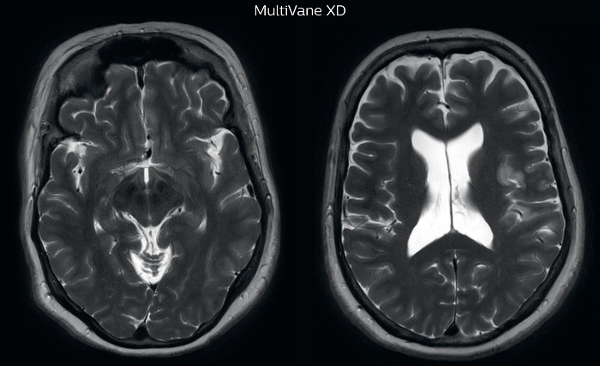

Motion-free imaging of white matter changes with MultiVane XD

“We saw MultiVane XD provide remarkable improvement, not only for artifacts caused by patient motion, but also for the extent of pulsation artifacts in the basal cisterns. Based on these results, we have added the MultiVane XD sequence to our brain studies,” says Dr. Nickerson.

“MultiVane XD is especially useful when imaging patients with diseases that cause white matter changes on T2-weighted images, such as MS, small vessel disease, vasculitis and sarcoidosis,” says Dr. Nickerson. “Many of these are only visible on T2-weighted or FLAIR images, and sometimes aren’t even seen with FLAIR images. However, when using MultiVane XD and we don’t see any motion on the rest of the scan, but still do see a signal abnormality, we can probably attribute that to a real disease process, rather than an artifact.”

MRI motion artifact reduction in brain

The images made with MultiVane XD show significant reduction in motion artifact compared to the T2-weighted images without MultiVane below them.

Scanned on Ingenia 3.0T